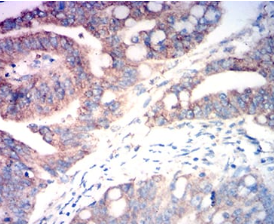

FAP Mouse Monoclonal antibody[5D9F6]

IHC    1/200 - 1/1000